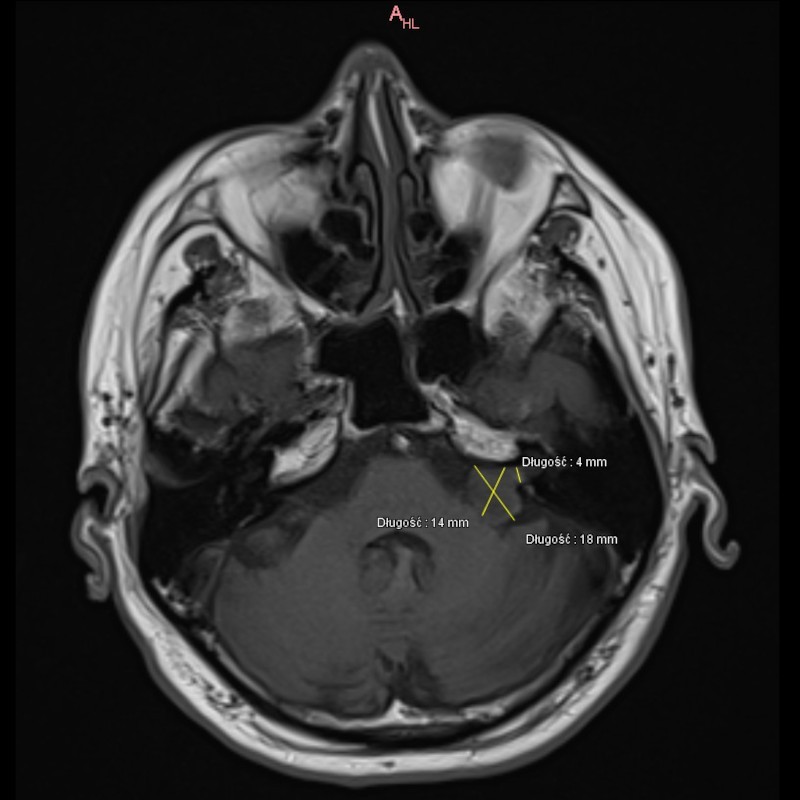

Po leczeniu (zdj. 2)

W kontrolnym badaniu MR z 06.04.23r: zmniejszył się guz lewego kąta mostowo-móżdżkowego. (zdj.2.). Chory ponadto zgłasza poprawę w zakresie zaburzeń równowagi (występują tylko w nagłej zmianie pozycji ciała) oraz ustępowanie niedosłuchu (od kilku miesięcy słyszy rozmowę przez telefon komórkowy przy uchu lewym, co było niemożliwe przed radioterapią).